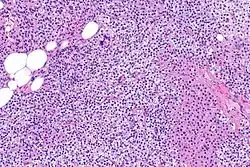

Primary hyperplasia of the parathyroid gland, results from both hypocalcaemia and increased phosphate levels by decreasing expression of calcium sensing receptors and vitamin D receptors at the parathyroid gland.[8][4] These decreases in receptor expression lead to hyperfunctioning of the parathyroid. Hyperfunction of the parathyroid gland is thought to exacerbate primary hyperplasia which evolves further to a secondary more aggressive hyperplasia. Histologically, these hyperplasic glands can be either diffuse or nodular.[24] Primary hyperplasia, usually resulting in diffuse polyclonal growth is manly related to reversible secondary hyperparathyroidism. Secondary hyperplasia of the parathyroid gland is more often a nodular, monoclonal growth that sustains secondary hyperparathyroidism and is the catalyst in the progression to tertiary hyperparathyroidism. Nodular hyperplastic glands in tertiary hyperparathyroidism are distinctly larger in both absolute size and weight up to 20-40-fold increases have been reported.[25][26][24]

Parathyroid glands are normally composed of chief cells, adipocytes and scattered oxyphil cells.[27][14] Chief cells are thought to be responsible for the production, storage and secretion of parathyroid hormone. These cells appear light and dark with a prominent Golgi body and endoplasmic reticulum. In electron micrographs, secretory vesicles can be seen in and around the Golgi and at the cell membrane. These cells also contain prominent cytoplasmic adipose.[27][14] Upon onset of hyperplasia these cells are described as having a nodular pattern with enlargement of protein synthesis machinery such as the endoplasmic reticulum and Golgi. Increased secretory vesicles are seen and decreased intercellular fat is characteristic.[27][24] Oxyphil cells also appear hyperplasic however, these cells are much less prominent.

Biochemically, there are changes in function between normal and nodular hyperplastic parathyroid glands. These changes involve proto-oncogene expression and activation of proliferative pathways while inactivating apoptotic pathways.[28] In nodular parathyroid tissue increased expression of TGF-a, a growth factor, and EGFR, its receptor, results in aggressive proliferation and further downregulation of vitamin D receptors, which act to suppress hormone secretions.[25][8][28] Furthermore, the proliferative marker, Ki67 is seen to be highly expressed in the secondary nodular hyperplastic state.[28][25] Tumour suppressor genes have also been highlighted as being silenced or degraded in nodular hyperplastic parathyroid tissue.[8][28] One such gene, p53, has been shown to regulate multiple tumour suppressor pathways and in tumorigenesis can be degraded by b-catenin. This pathway, in some aspect, is mediated by CACYBP, which is highly expressed in nodular parathyroid hyperplasia.[28]